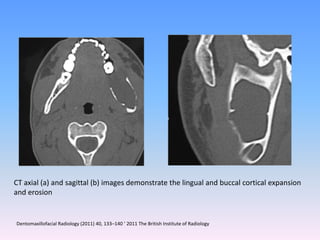

CT axial (a) and sagittal (b) images demonstrate the lingual and buccal cortical expansion

and erosion

Dentomaxillofacial Radiology (2011) 40, 133–140 ’ 2011 The British Institute of Radiology